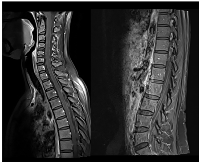

Figure 1

CE MRI at BM and LMC initial moment of diagnosis.

Heterogeneous space-occupying lesion (right posterior parietal-parasagittal cortico-subcortical area), with vasogenic edema and sulcal effacement, compatible with a BM lesion, along with pachymeningeal carcinomatosis (right next to the first described BM).

Sixteen months later (1.3 years), the patient was admitted to the emergency department with severe right headache (only mild response to pain medication and presence of other red flags: vomiting, night awakening, neurological deficits - visual deficits, facial paresthesias, dizziness; vertigo and decreased left upper limb muscular strength). Cranioencephalic computed tomography (CE-CT) showed a heterogeneous space-occupying lesion, in the right posterior parietal-parasagittal cortico-subcortical area, with vasogenic edema and sulcal effacement, compatible with a new BM lesion. Cranioencephalic magnetic resonance imaging (CE-MRI) confirmed the lesion genesis, showing new pachymeningeal carcinomatosis (right next to the lesion) and disseminated leptomeningeal carcinomatosis (LMC) (extended to cerebellar fissures, midbrain and brachiocephalic bridge, involving the cranial nerves emergence as well) (Figure 1). An important mass effect was present, compressing and occluding the right vertebral artery V4 terminal segment. Neuraxis MRI confirmed disseminated LMC in all neuraxis (extension to the conus medullaris limit) (Figure 2). Lumbar puncture showed a turbid cerebrospinal fluid (CSF), with cytology demonstrating small, scattered lymphocytes, large epithelial cells exhibiting irregular, hyperchromatic nuclei, and the presence of the ‘cell-in-cell’ phenomenon. The fluid was histologically confirmed as central nervous system (CNS) metastasis of HER2 positive BC. Re-staging showed neither local nor distant disease.